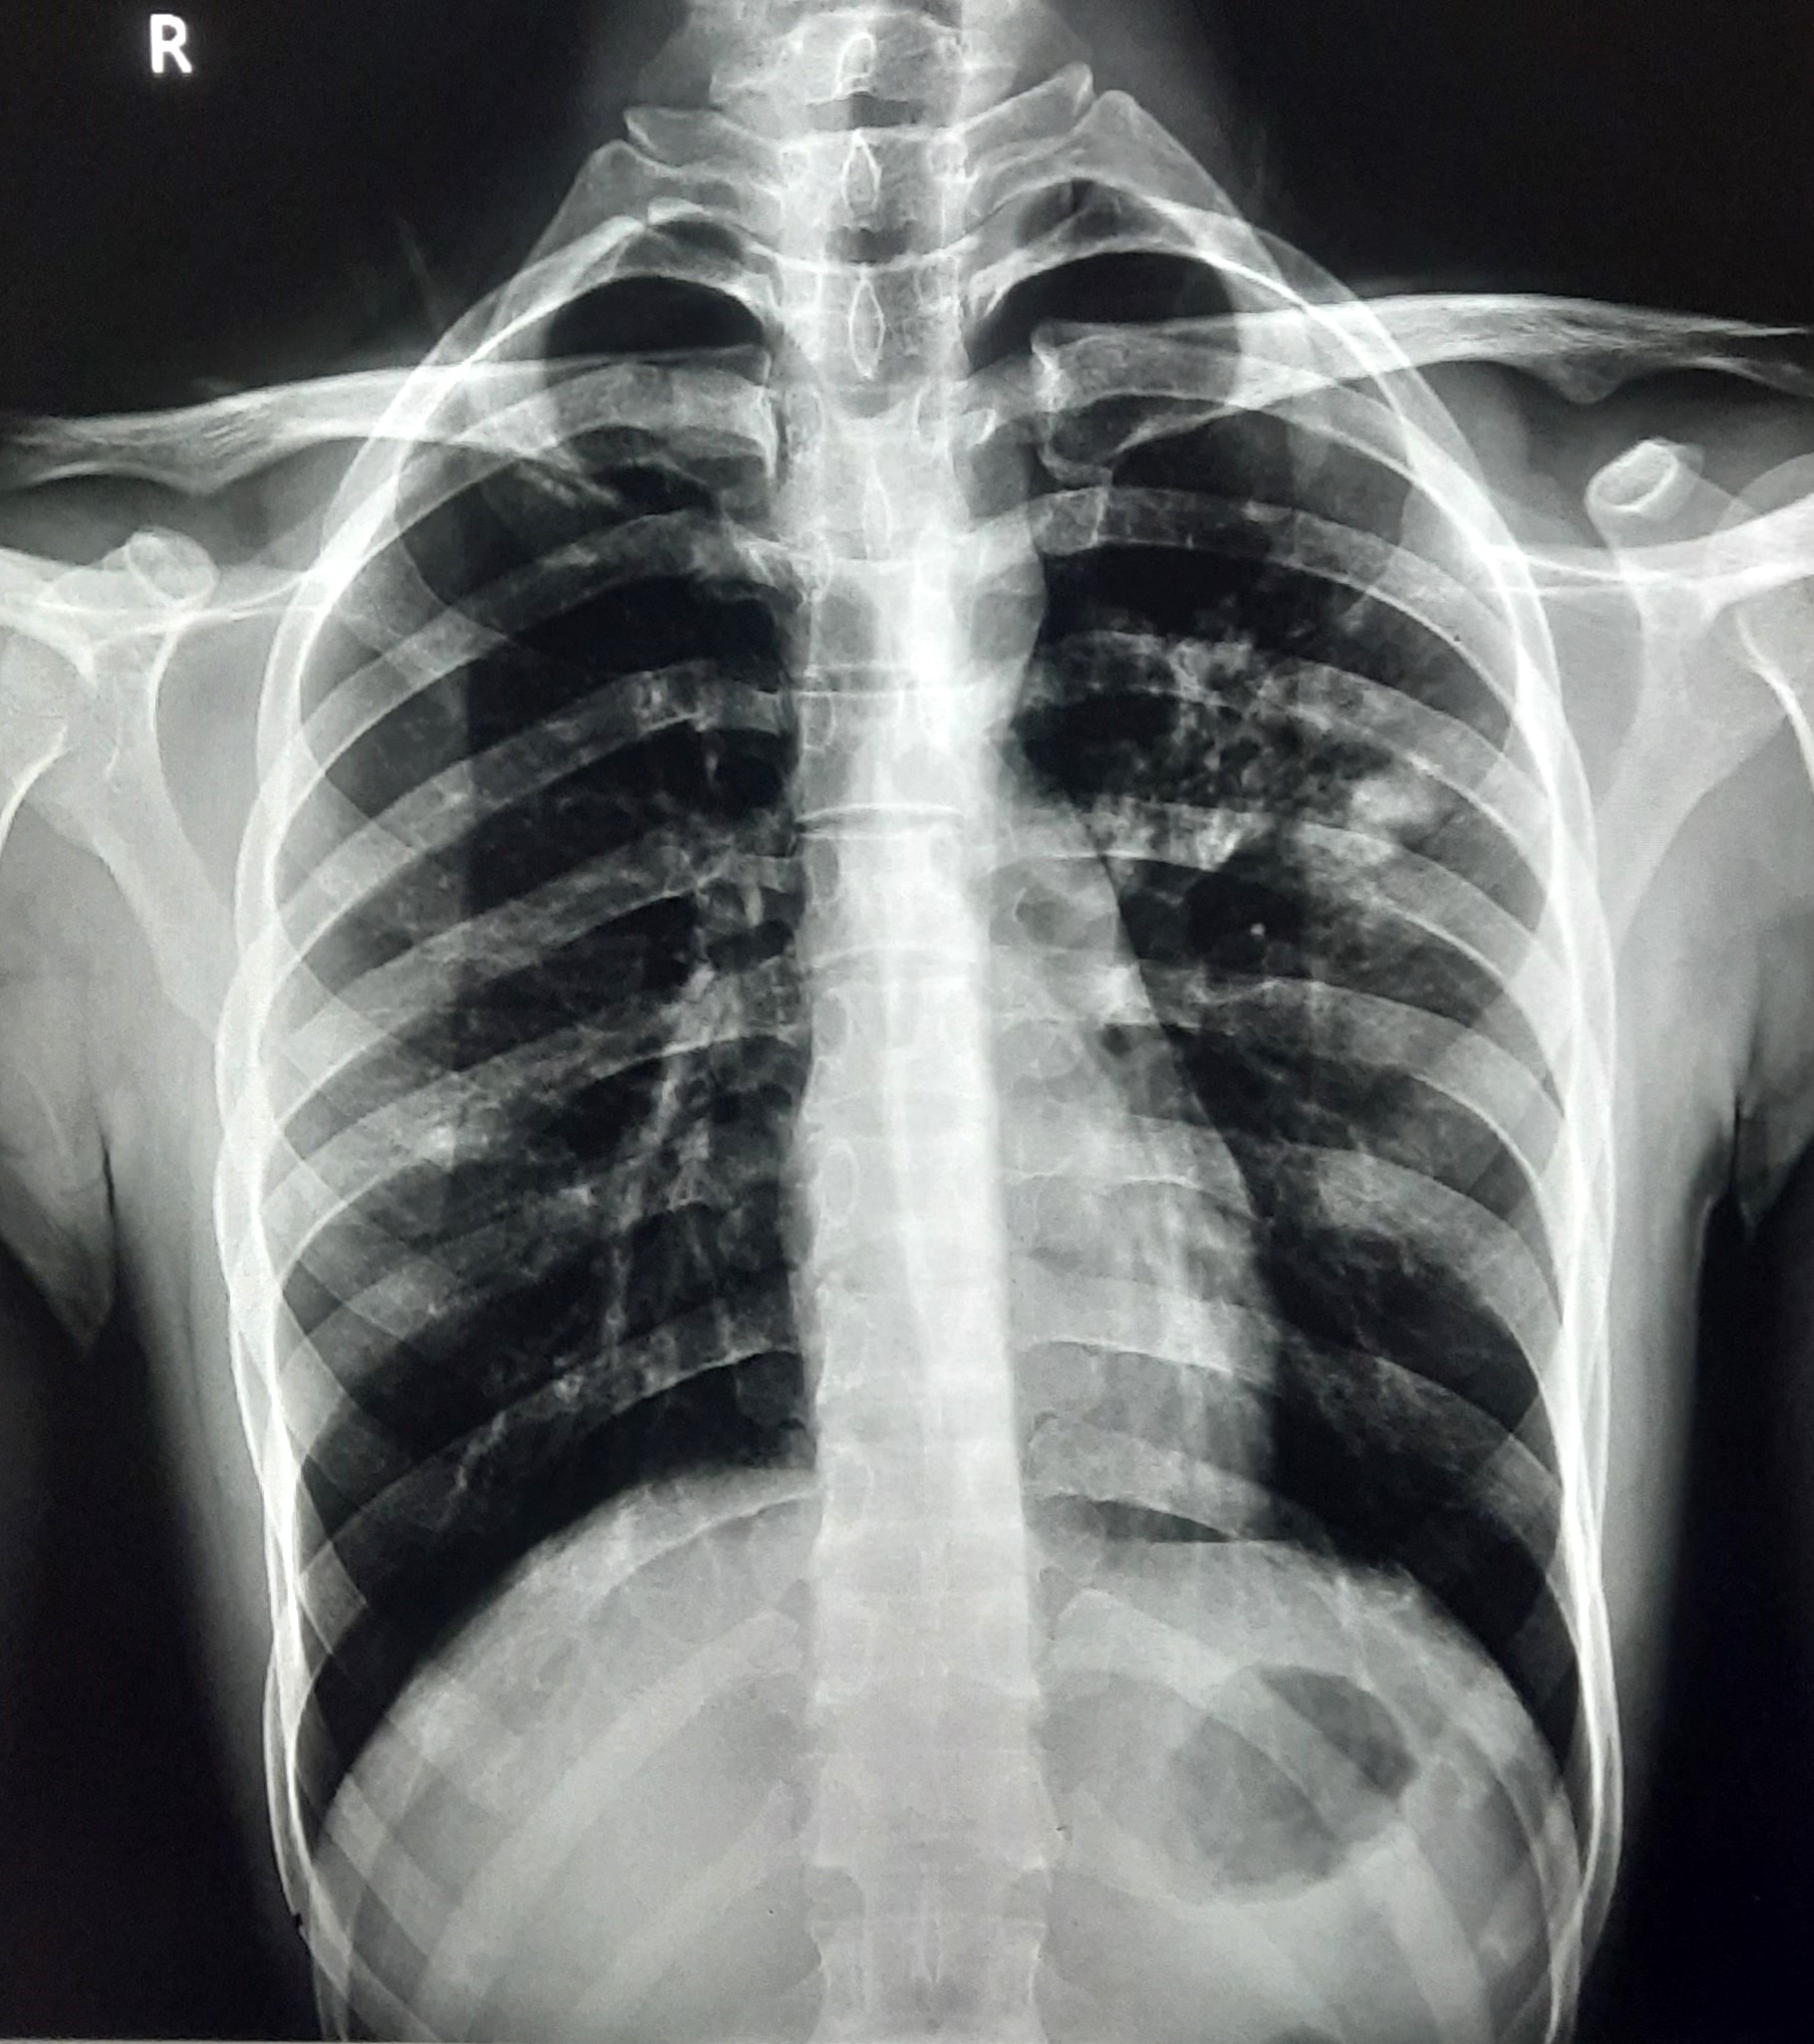

| 151 | IGGMC, Nagpur, Nagpur | P2 | 29-4321 | Chanda Bhowate | Consent taken on Paper | 42 Yrs. |

Provisional Diag : ?

Final Diag : (CxR- Right Sided Synpneumonic Effusion With Pulmonary Infiltration) |

Result awaited (Suspected TB/Non-TB) | Right CP Angle Blunting With Right Lower Zone In-Homogenous Opacity Present With Right Middle Zone/ Lower Zone Infiltration Present | Abnormality visible on x-ray |